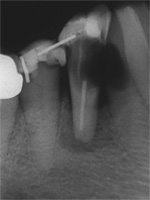

Aufbissempfindlichkeit an 33 veranlasste uns erstmalig in dieser Kieferregion zu röntgen. Mit grossen Augen sahen wir dann an, was uns auch ansah. Einen Knochendefekt dieser Grössenordnung mit seiner schaurigen Aura sieht man zum Glück nicht jeden Tag. Doch, obgleich das Alien dereinst Zahn 34 entsprang, war eine Behandlung nur am Zahn davor durchsetzbar. Dessen Wurzelfüllung erfolgte regulär nach 14 Tagen, neue Terminangebote aber wurden, weil angeblich nicht mehr nötig, verschmäht.

Keine 8 Wochen gingen noch in's Land, bis das mit Macht geschah, was lange schon erwartet war. Das Arbeitsprogramm bestand aus Eröffnung von Zahn 34 und einer Schwellung inkl. Drainage, am nächsten Tag dann noch Aufbereitung des Kanals mit Einlage. 2 Wochen später dann die Füllung plus einem als Resektion deklarierten Auslöffeln des Granu­lationsgewebes durch eine Mini-Öffnung, zu deren Verschluss eine Naht genügte.

3 Aufnahmen sind von 2001, die vierte vom Nov. 2006